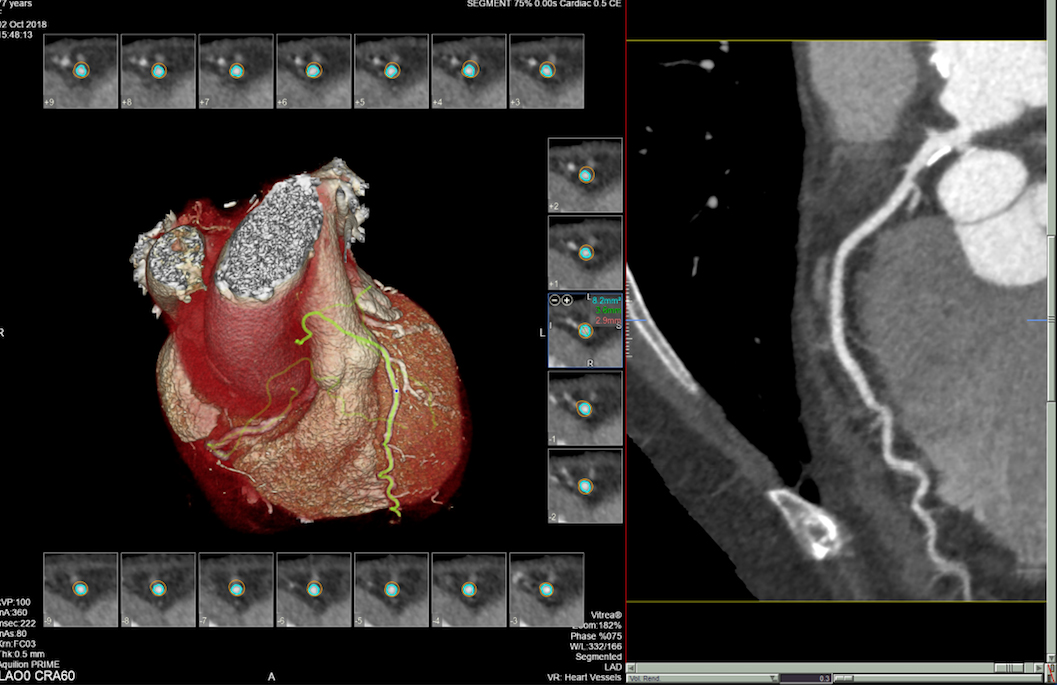

- MSCT koronarografija (prikaz krvnih žila srca CT-om, bez neugodnosti i komplikacija koje nosi klasična koronarografija), u saradnji s Poliklinkom dr.Al-Tawil